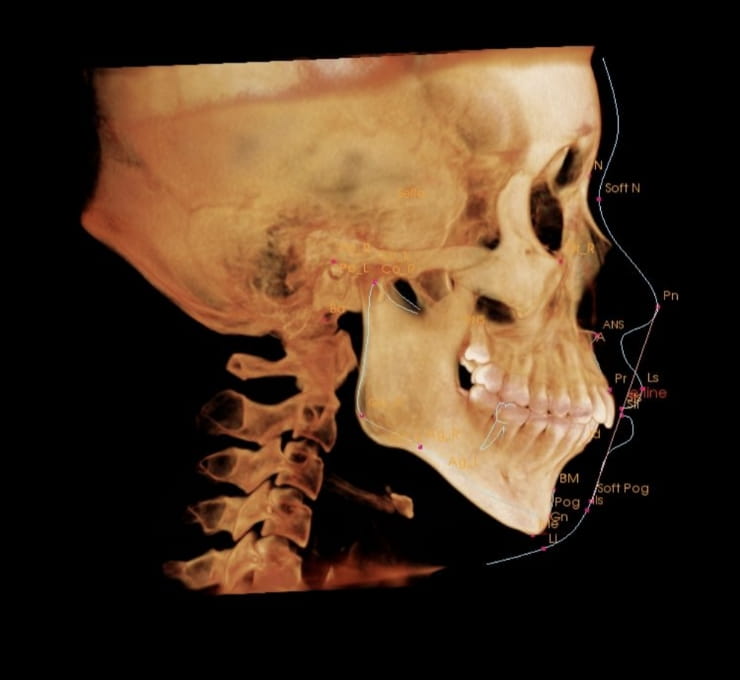

3D CT|

骨格・骨密度の立体把握

セファロ|

前突量を数値で計測

POINT 01

CTデータで「安全な移動量」を事前に把握する

勘に頼らない、データに基づく治療設計。CT撮影で骨の厚み・歯根の傾きを3D分析することで、無理な移動による歯ぐきの退縮リスクを事前に防ぎます。抜歯の可否も画像と数値で丁寧にご説明します。

「骨が薄い部分を無理に動かすと歯ぐきが下がる」——このリスクをCTで特定し、安全な移動経路を設計してから治療をスタートします。